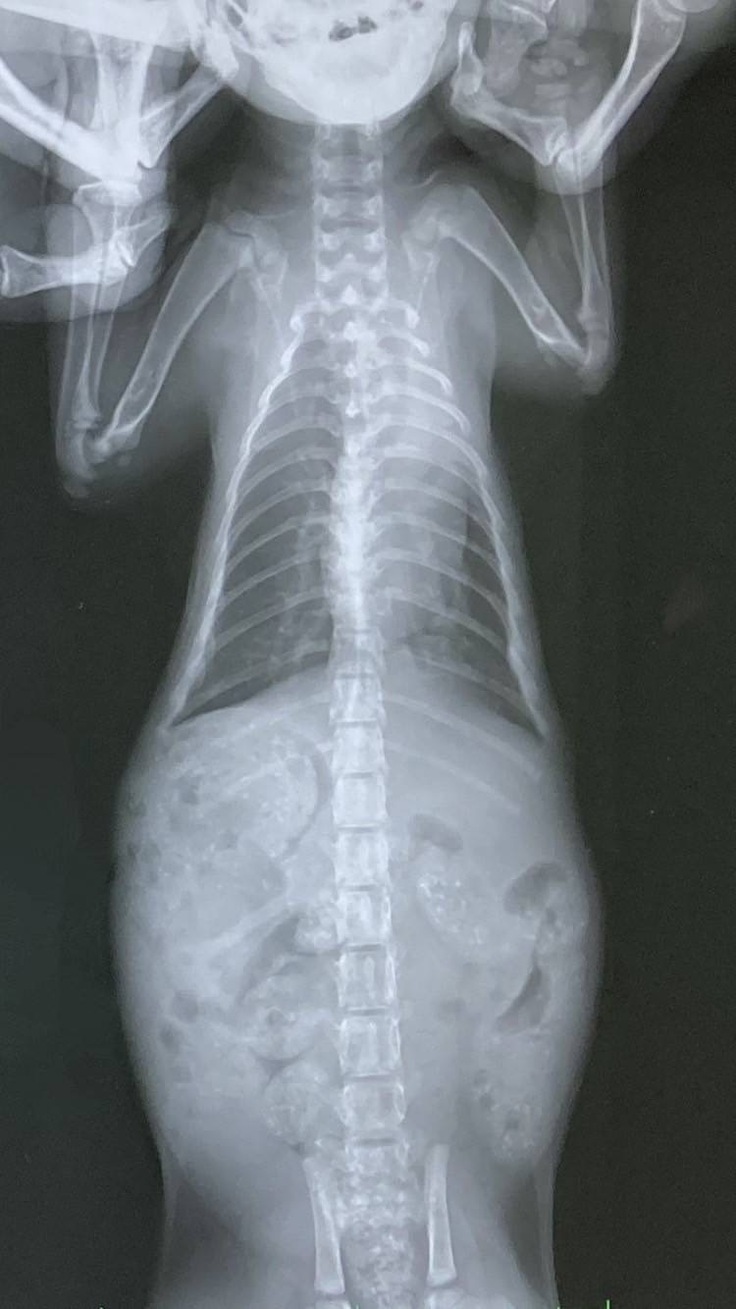

子猫ちゃんたちの通院日で診察とレントゲンを撮ってもらいました。体重が2匹とも900gで標準よりも少し大きいぐらいだと言われました。肺炎は分かりにくいけれど、少しずつ良くなっていると思う、ナイトの漏斗胸も良くなってきているから軽度のままでいけるのではないかと嬉しいお言葉をいただくことが出来ました。